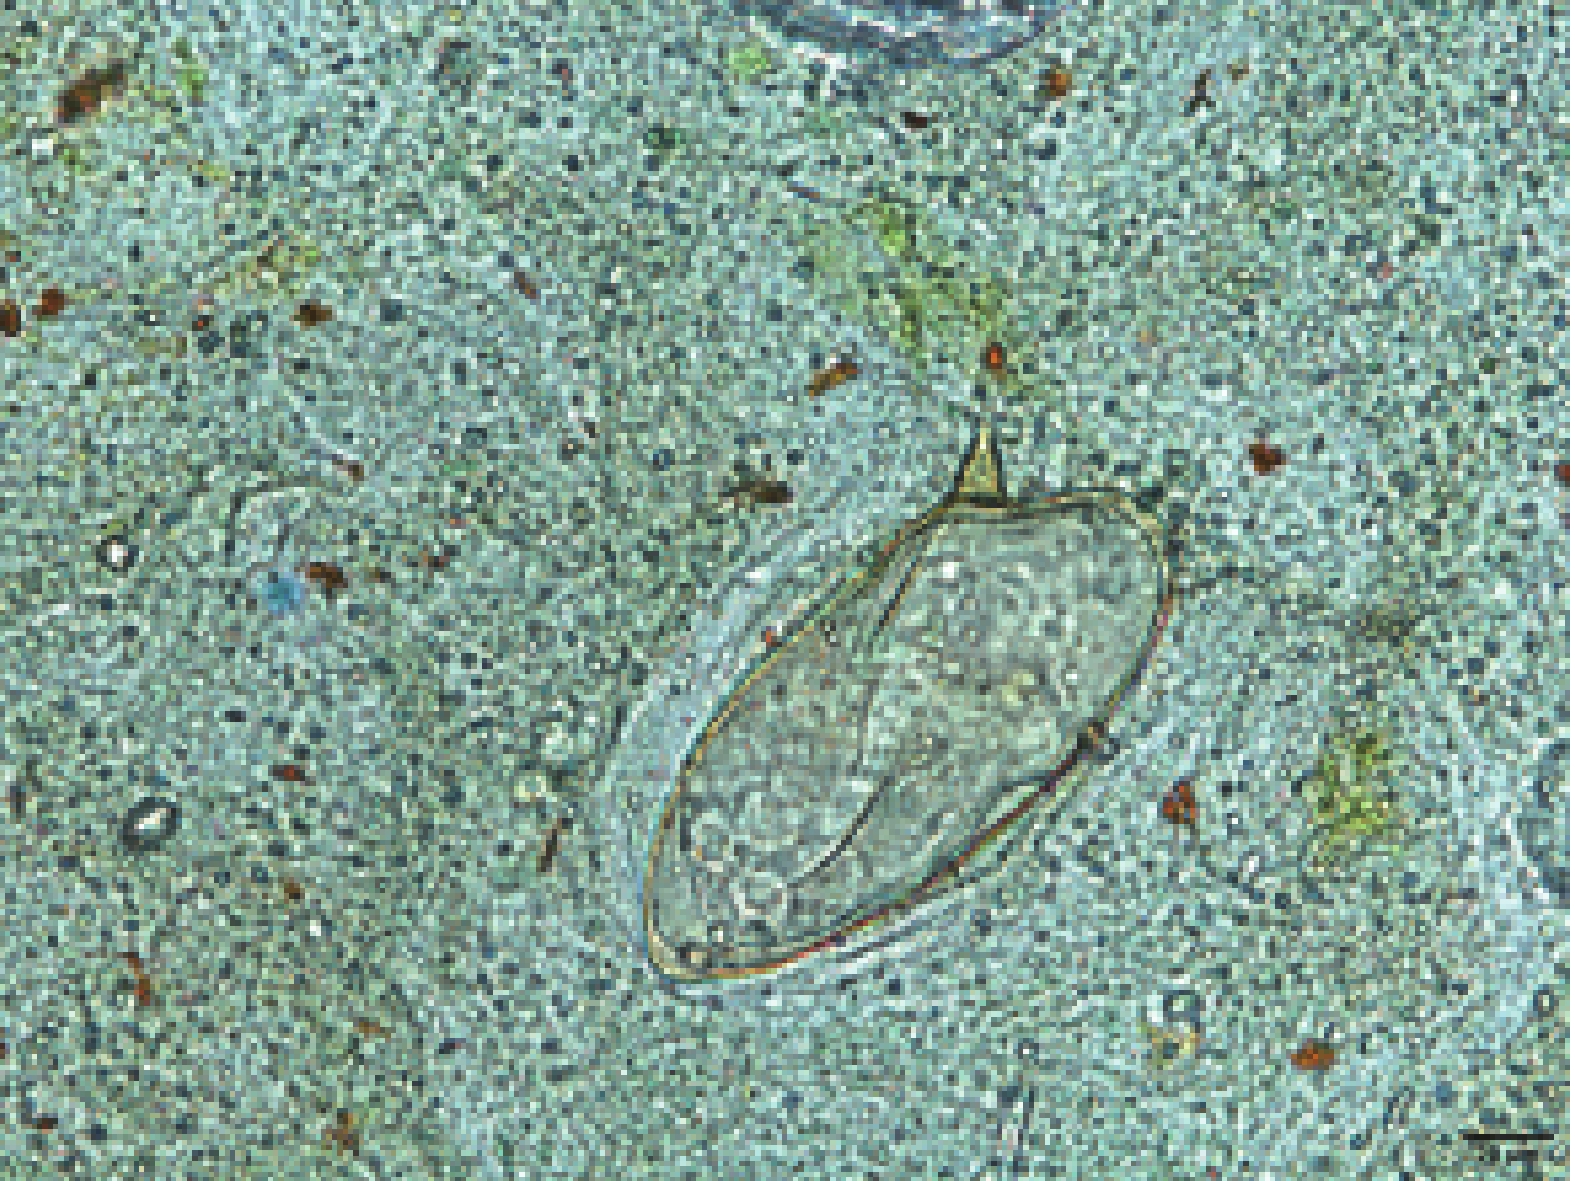

Abbreviation: MRI=magnetic resonance imaging.Routine blood testing demonstrated marked eosinophilia, with both the percentage (25.0%) and absolute count (3.30×109/L) exceeding normal reference ranges. HTS analysis of blood samples identified four sequences of S. mansoni. Fecal examination employed three methods: automated routine analysis, the egg-hatching method following nylon mesh bag concentration, and the modified Kato-Katz thick smear technique. Automated stool analysis failed to detect any eggs, and the egg-hatching method revealed no miracidia. Using the Kato-Katz technique, examination of three fecal smears yielded no S. mansoni eggs; however, continued testing of an additional seven smears (10 total) identified a single egg (Figure 2). These combined findings provided definitive etiological evidence for diagnosis.

Figure 2.Egg detected at Kato-Katz thick-smear preparations, 400×magnification.

Note: The lateral subterminal spine is the character of S. mansoni eggs.Epidemiologically, the patient had worked in schistosomiasis-endemic regions, including Angola from 2013 to 2024, and the Democratic Republic of the Congo (DRC) from December 2024 to April 2025. While in the DRC, the patient had frequent contact with local mountain spring water, which served as the primary source for both drinking and daily household use. Although intermediate host breeding grounds have emerged in southern China, the country remains non-endemic for schistosomiasis mansoni. Consequently, this case represents an S. mansoni infection acquired in Africa.

Definitive diagnosis of S. mansoni infection requires detection of S. mansoni eggs or miracidia in fecal examinations or tissue biopsies (13). The Kato-Katz thick smear technique represents a widely used method for detecting parasite eggs in stool samples and remains suitable for laboratory diagnosis of most intestinal parasitic infections. In this case, direct smear examination and nylon mesh bag concentration failed to detect pathogens, and only a single egg was identified in one Kato-Katz slide among ten slides examined. Given that S. mansoni produces only one-fifth to one-tenth the number of eggs compared with Schistosoma japonicum, this low egg burden presents significant diagnostic challenges that laboratory personnel must recognize. Furthermore, HTS has demonstrated an invaluable role in guiding clinical diagnosis of rare or atypically presenting parasitic infections (14-15).